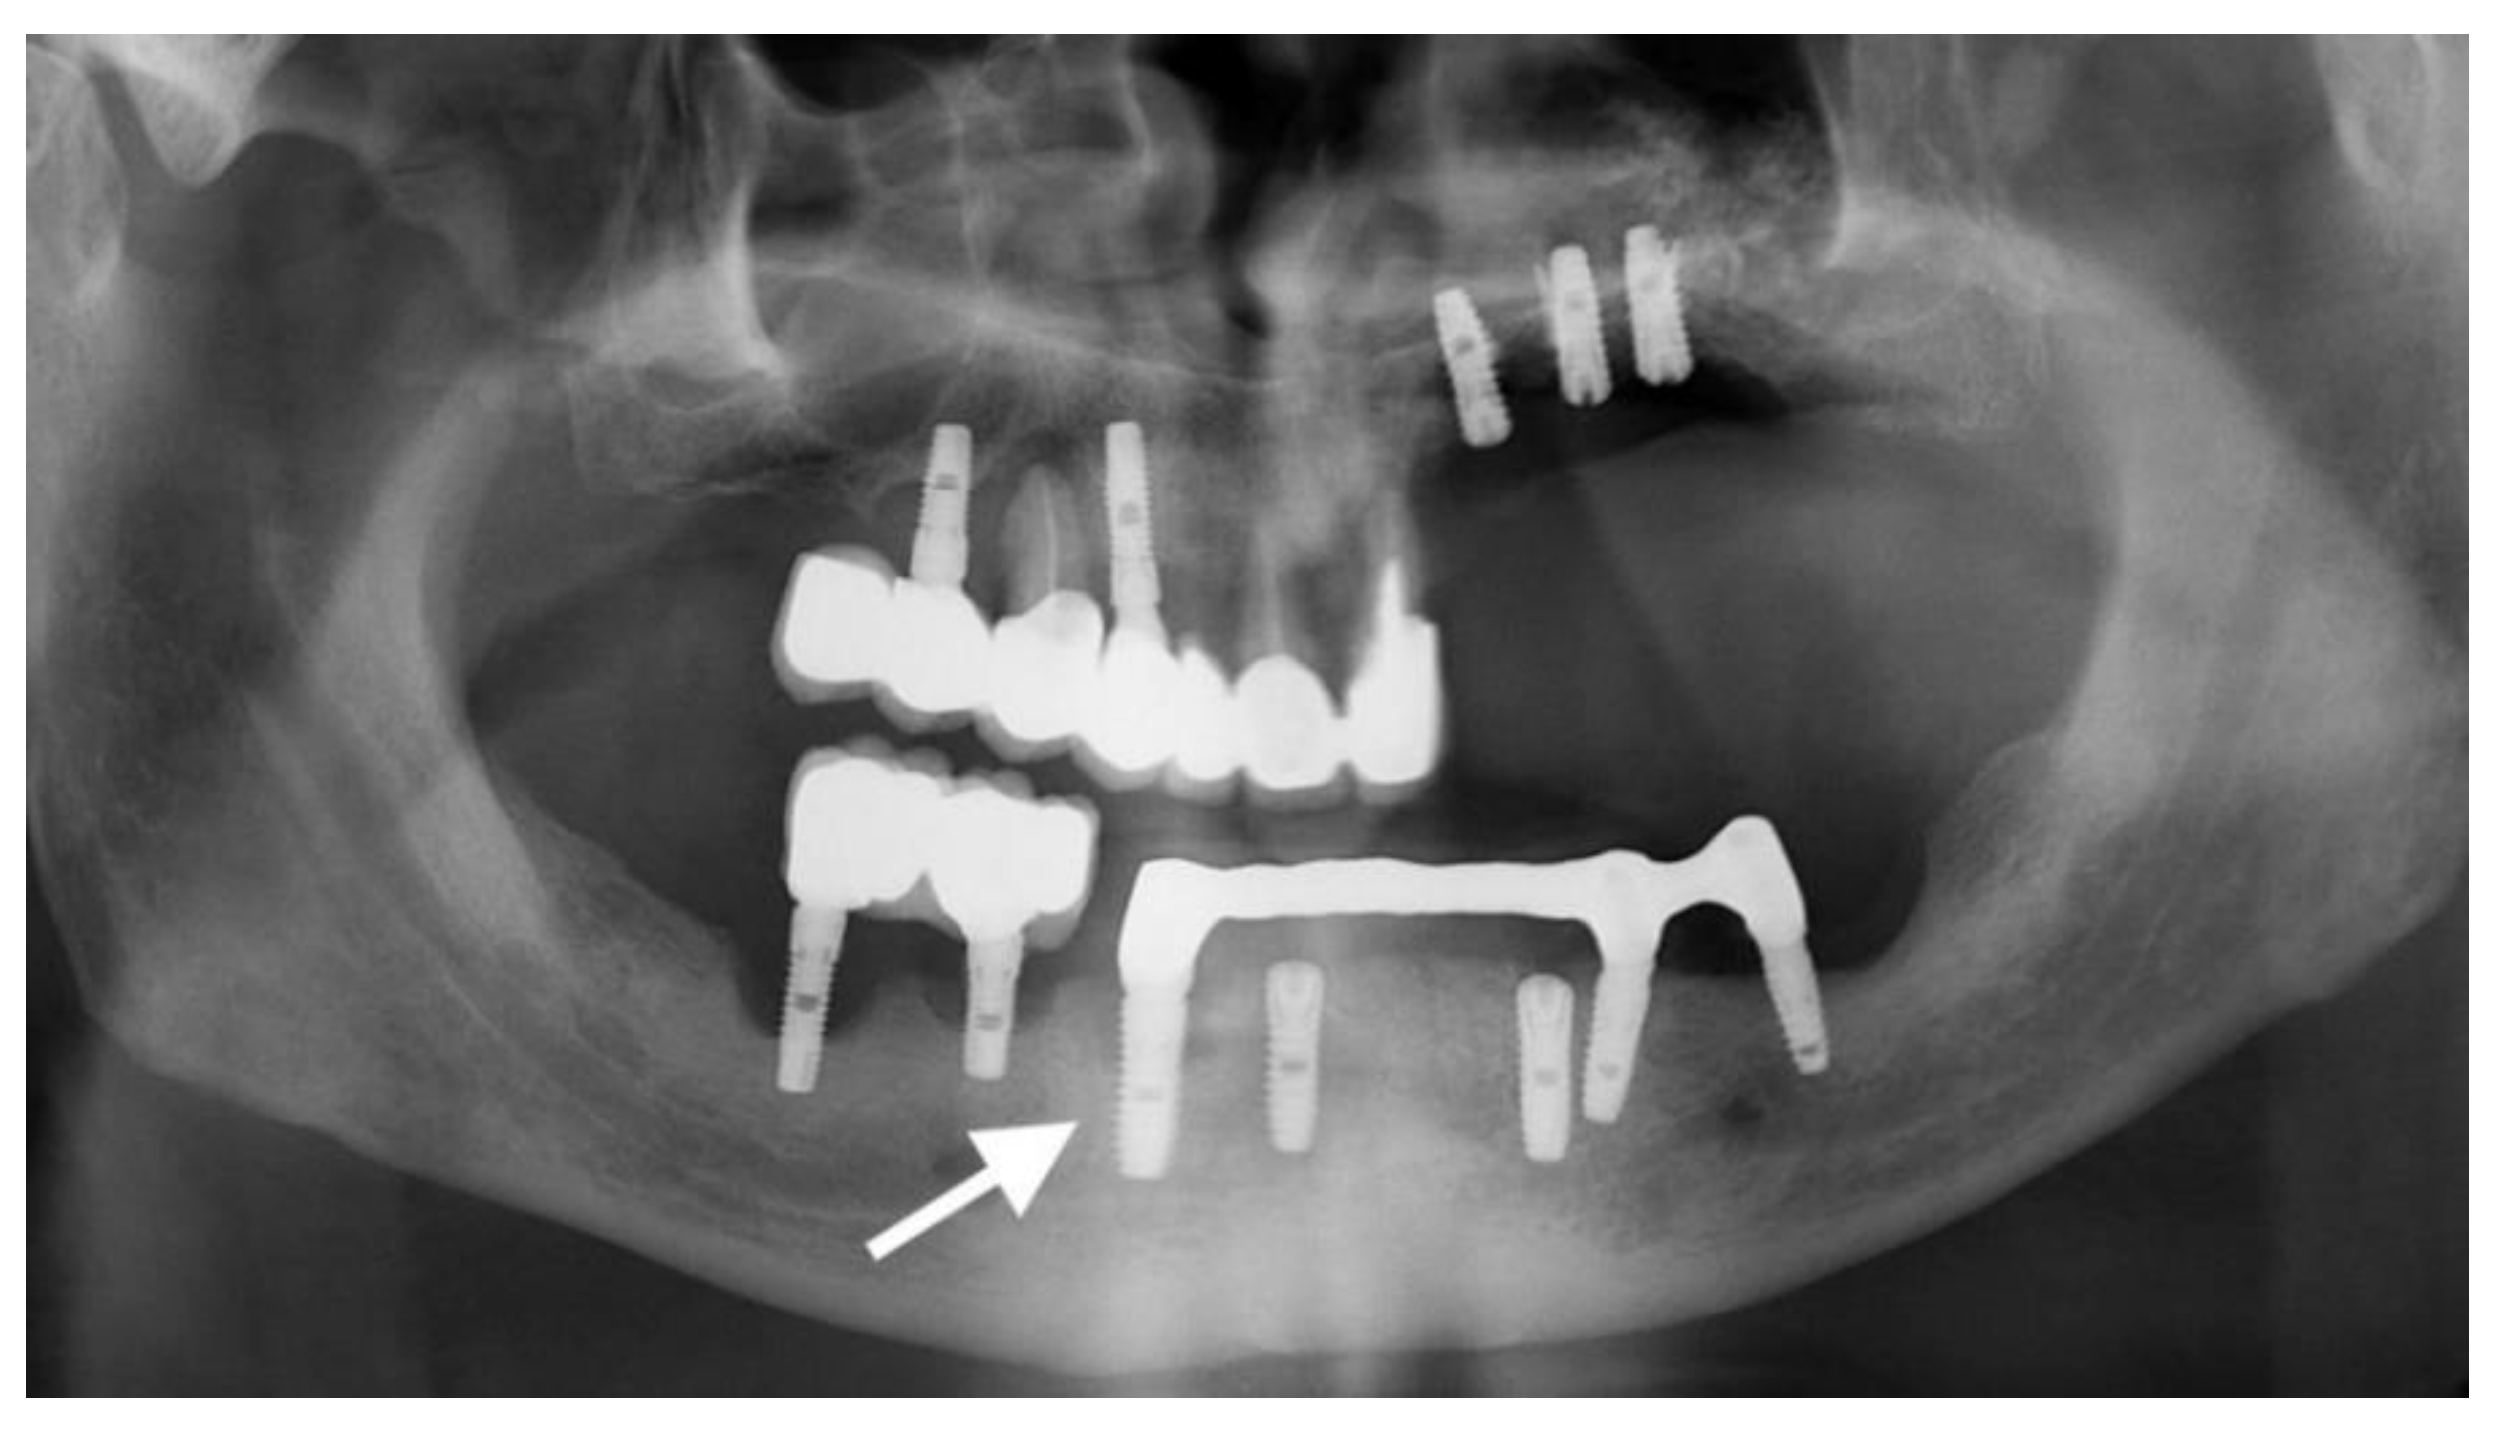

2.1. Materials

3.1. Dental Implants